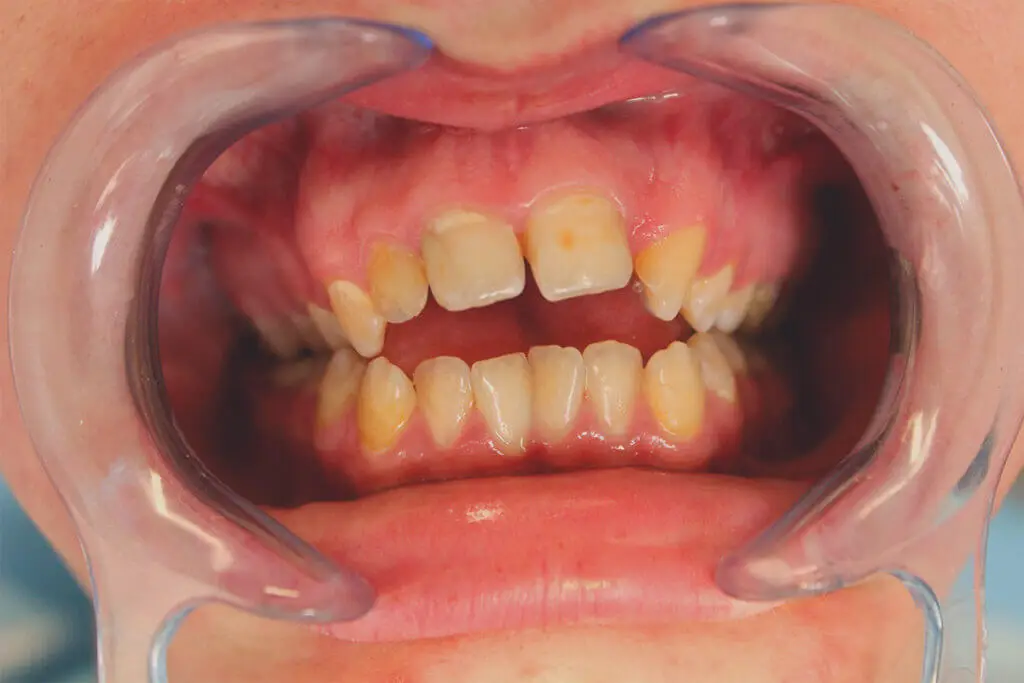

Róbert fiatal férfi páciens, tanuló. Komplex problémával keresett fel, diagnózisa során kiderült, hogy nyitott harapása mellett kétoldali keresztharapása is van, illetve bal felső második kismetsző fogát korábban eltávolították.

A kezelés során több lépcsőben oldottuk meg az eltérést, a fogszabályozó levétele után cirkon híddal pótoltuk a hiányzó fogat és a nagy kiterjedésű tömésekkel rendelkező front fogakat.